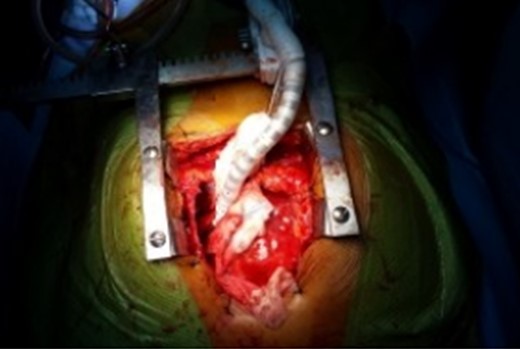

The cysts were approached through a median sternotomy incision. The pericardium was dissected free of the heart and major vessels. The cyst lateral to the aorta was excised first. Hypertonic (3.0%) saline was injected and the cyst fully excised. The anterior surface of the ectocyst was also excised. In order to expose the posterior cyst, the heart was lifted up, rotated to the right and maintained in this position by the Octopus IV cardiac stabilizer (Figs 2 and 3). The cyst was dissected free of the pericardium but remained adherent to the myocardium. The edges of the cyst were packed with small gauze soaked with hypertonic saline. Then, the cyst was injected with hypertonic saline. After 5 min, the cyst was opened and fully excised. The floor (posterior surface) of the cyst was widely excised leaving the residual cavity widely opened to the pericardial sac. Size 28F chest drains were inserted in the residual cavities, and the wound was closed in the routine way. The patient progressed well and was discharged home on the fourth postoperative day.

Intraoperative photograph of the Octopus IV cardiac stabilizer maintaining the position of the heart to expose the posterior hydatid cyst.